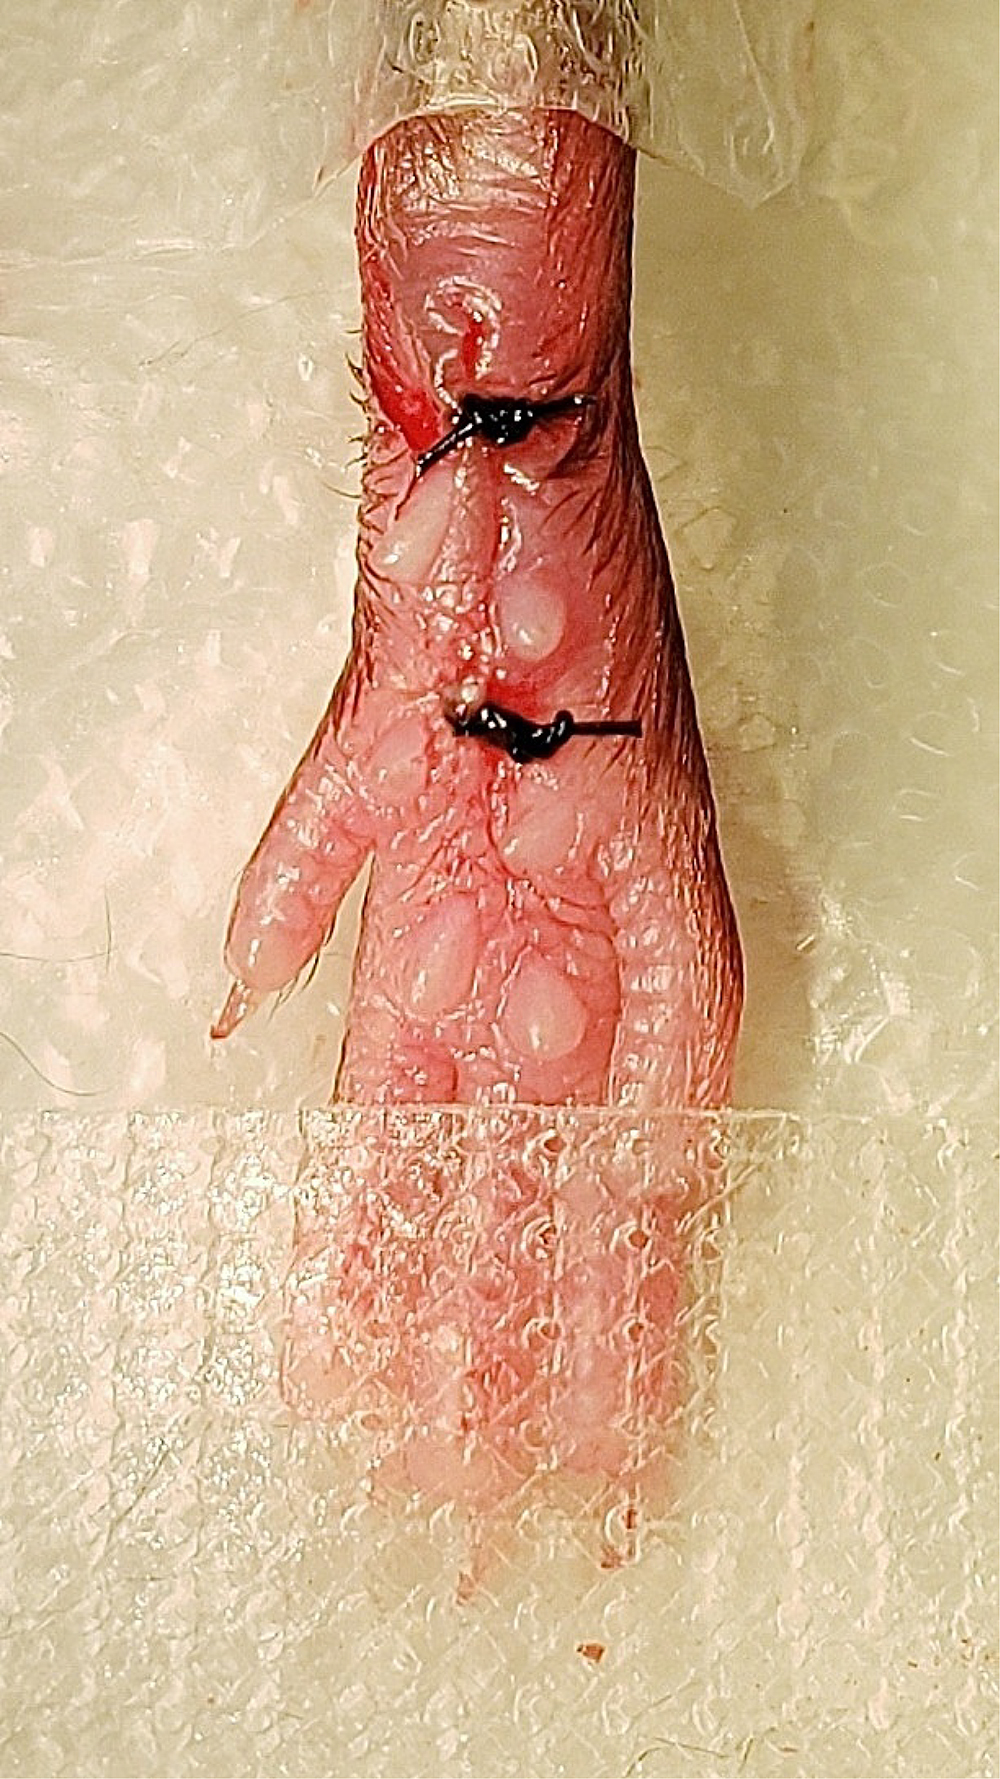

Figure 7. Muscle incision. A longitudinal incision was made through the muscle belly of the elevated flexor digitorum brevis muscle from proximal to distal ends of the cutaneous incision. - To suture the wound, remove the curved forceps from underneath the muscle and elevate the edges of the skin surrounding the wound with forceps. Close the wound by putting two sutures in the skin (but not muscle) approximately 2 mm apart using 5-0 nylon sutures and a hemostat (Figure 8).

Figure 8. Cutaneous suturing. The skin was closed with two 5-0 nylon sutures. - Apply a generous amount of bacitracin ointment to the wound using a cotton swab and place the mouse in the new cage located on the Heat Therapy Pump pad from Step 2.